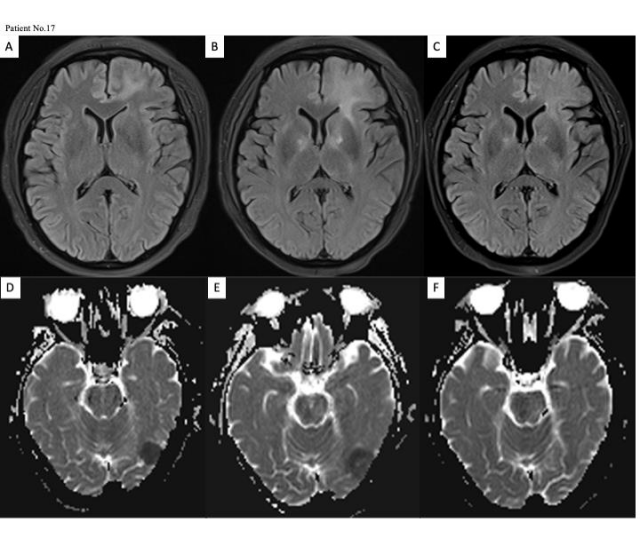

图1展示的是一例患者治疗前后的中枢影像学对比。

图1.MRI磁共振成像显示患者的图像

A是在CAR-T细胞输注前;B在CAR-T细胞回输+30天;C在CAR-T回输后+3个月,病灶已完全消失。